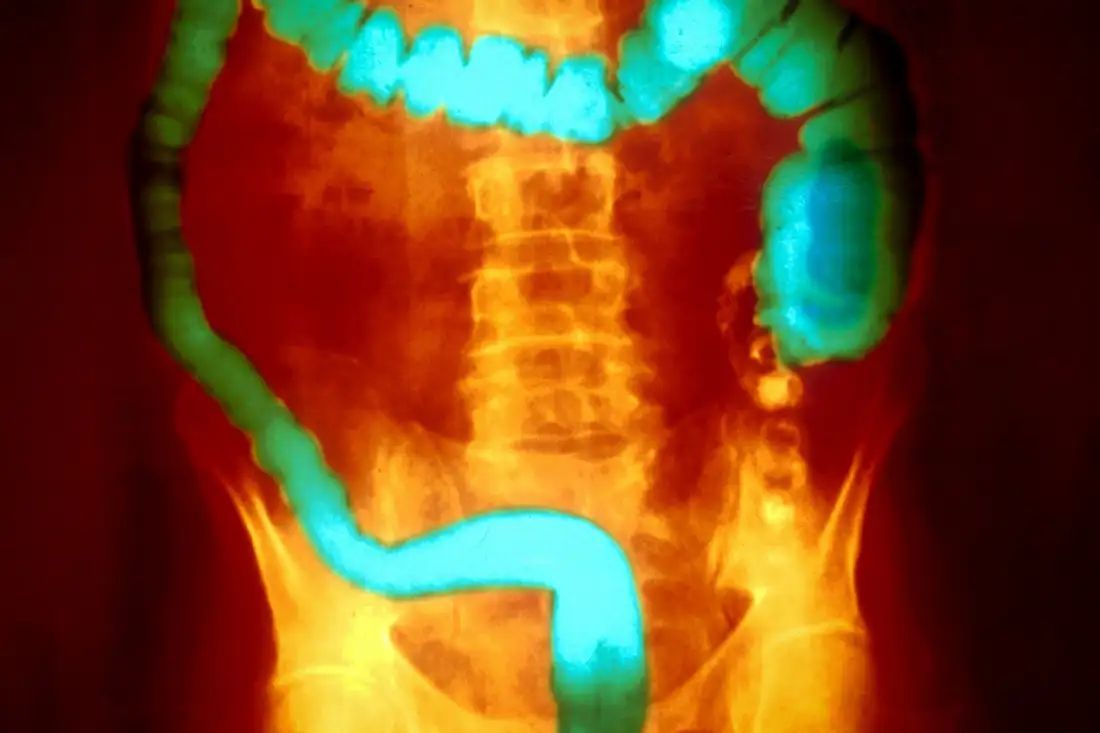

Порівняння тканин людей з колітом показало значне зменшення кількості макрофагів. Експерименти на мишах підтвердили: їхнє знищення робить тварин набагато чутливішими до коліту. Токсин продукують певні штами Aeromonas, відомі як MTB. Дослідники виявили ці бактерії у 72 % пацієнтів із колітом, тоді як серед здорових людей показник становив лише 12 %. Це демонструє виразну асоціацію між токсином і хронічним запаленням кишечника.

Коли мишей заражали MTB, коліт розвивався швидше, проте модифіковані бактерії без аеролізину не мали такого ефекту. Це підтвердило ключову роль токсину. Мартін Крігель зауважив: «токсин MTB порушує імунітет кишечника, виснажуючи спеціальні макрофаги». Водночас він наголосив, що вплив можуть посилювати й інші бактерії, адже після повного очищення кишкового мікробіому ефект зникав.